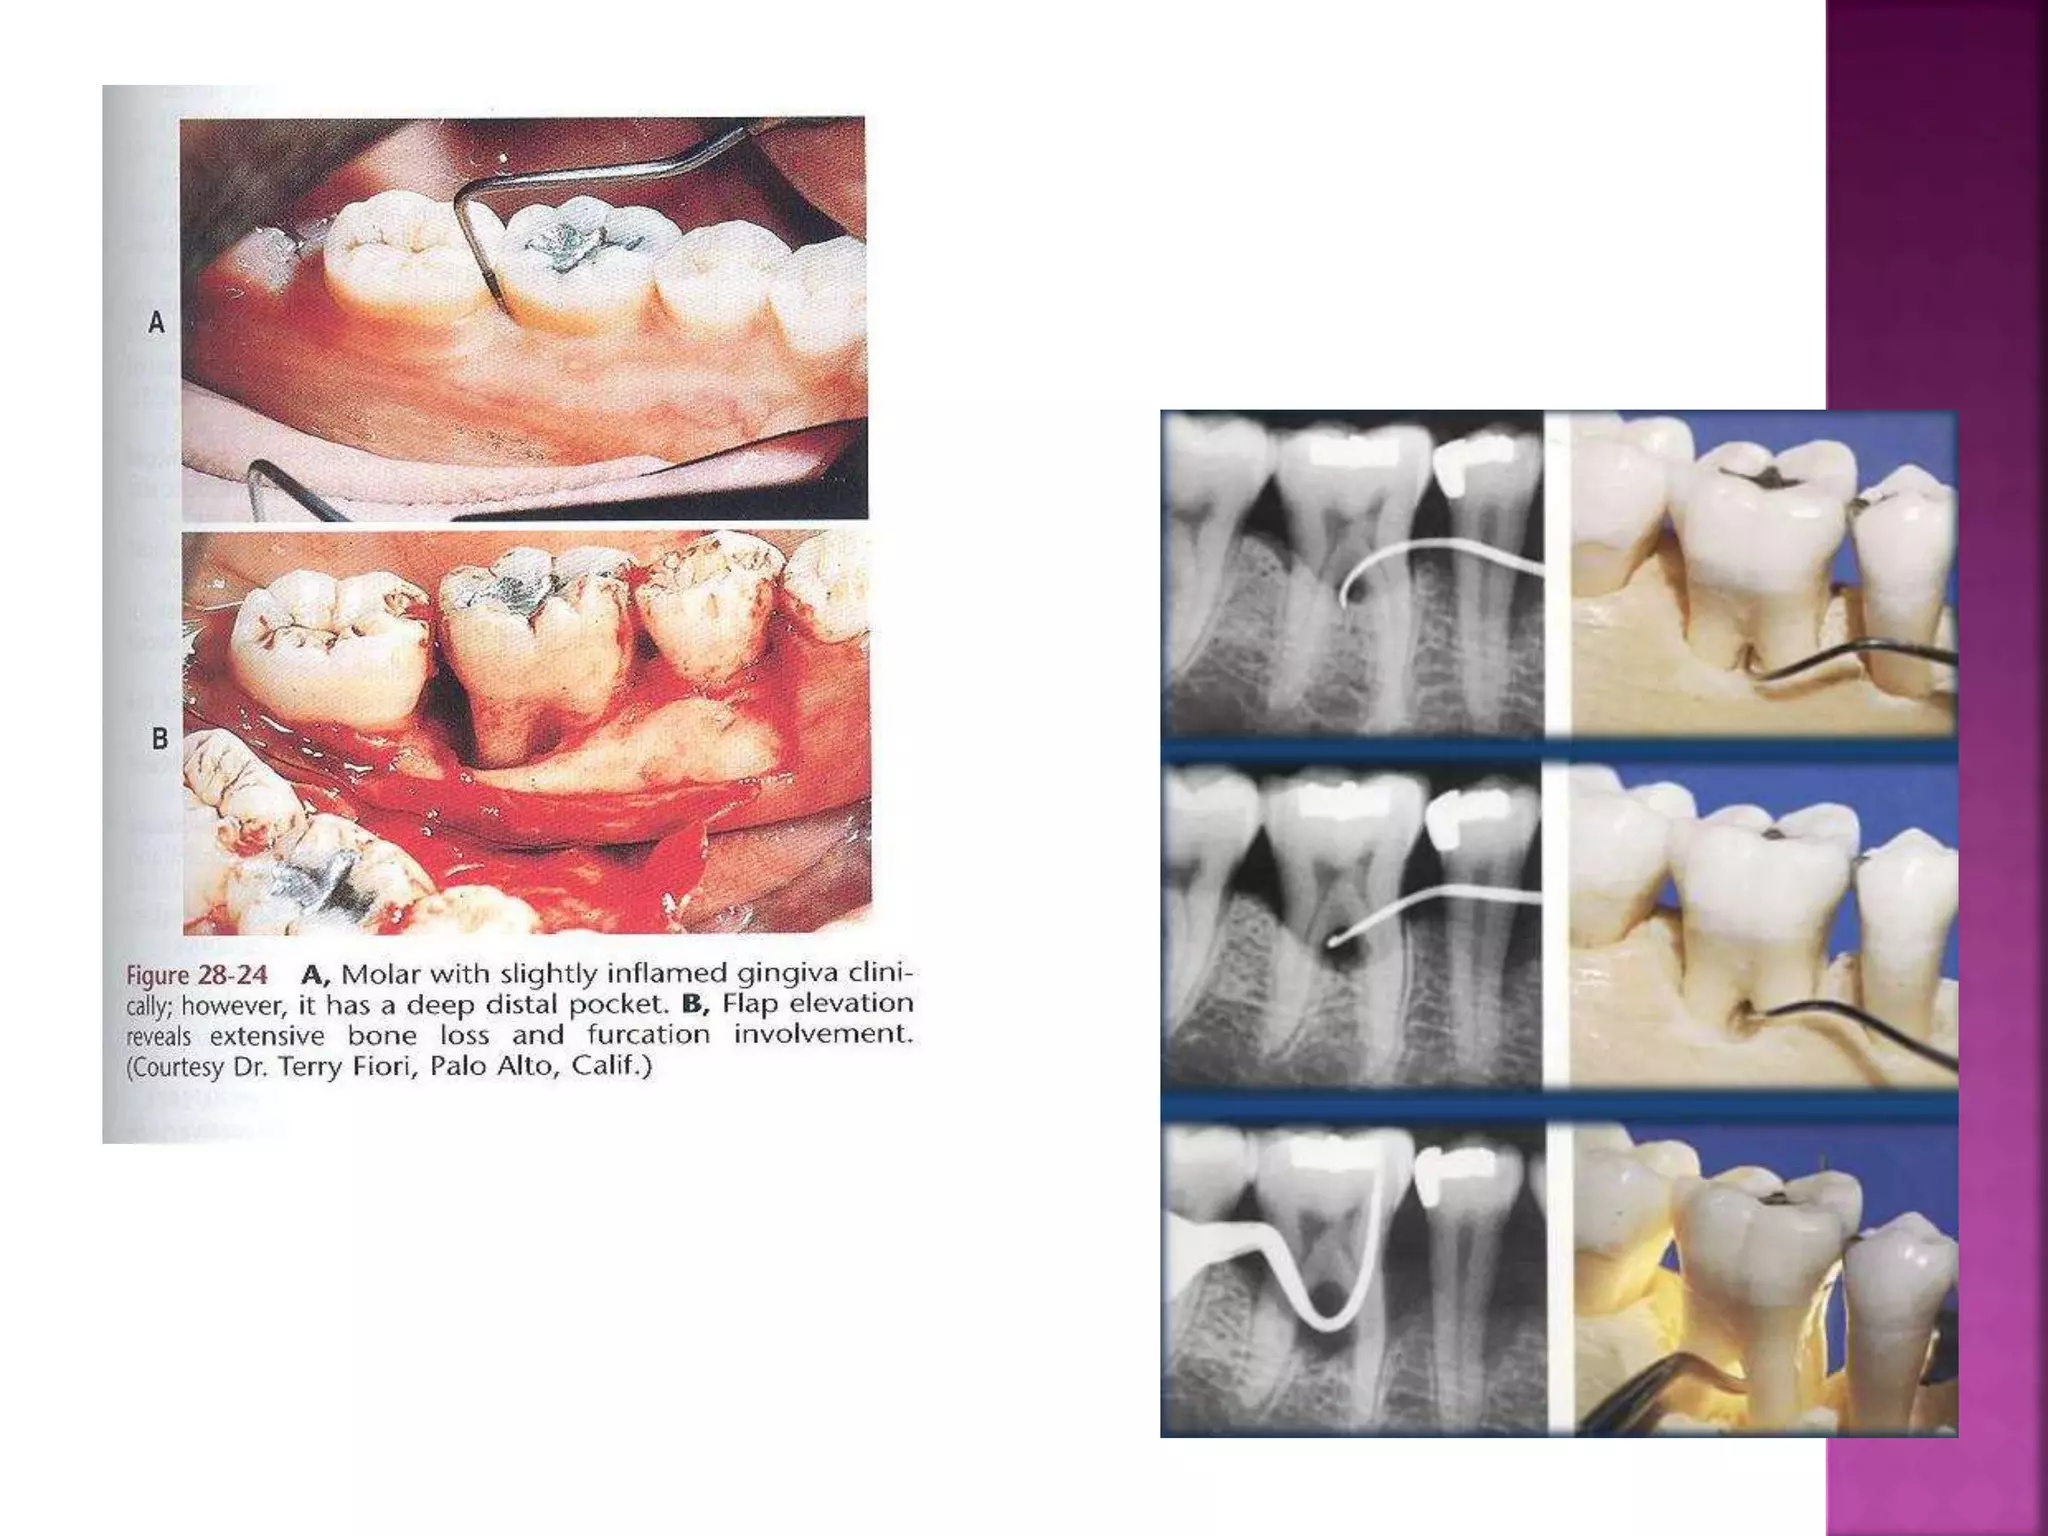

This document summarizes the classification of osseous defects caused by periodontal disease. It describes different types of horizontal bone loss including osseous craters and bulbous bony contours. It also discusses vertical/angular bone loss and classifications proposed by Glickman and Goldman/Cohen. Furcation involvement is classified using scales proposed by Glickman and Tarnow/Fletcher. Understanding the nature of these bone alterations is important for effective diagnosis and treatment planning.